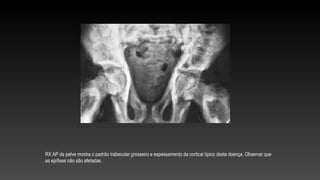

RX AP da pelve mostra o padrão trabecular grosseiro e espessamento da cortical típico desta doença. Observar que

as epífises não são afetadas.